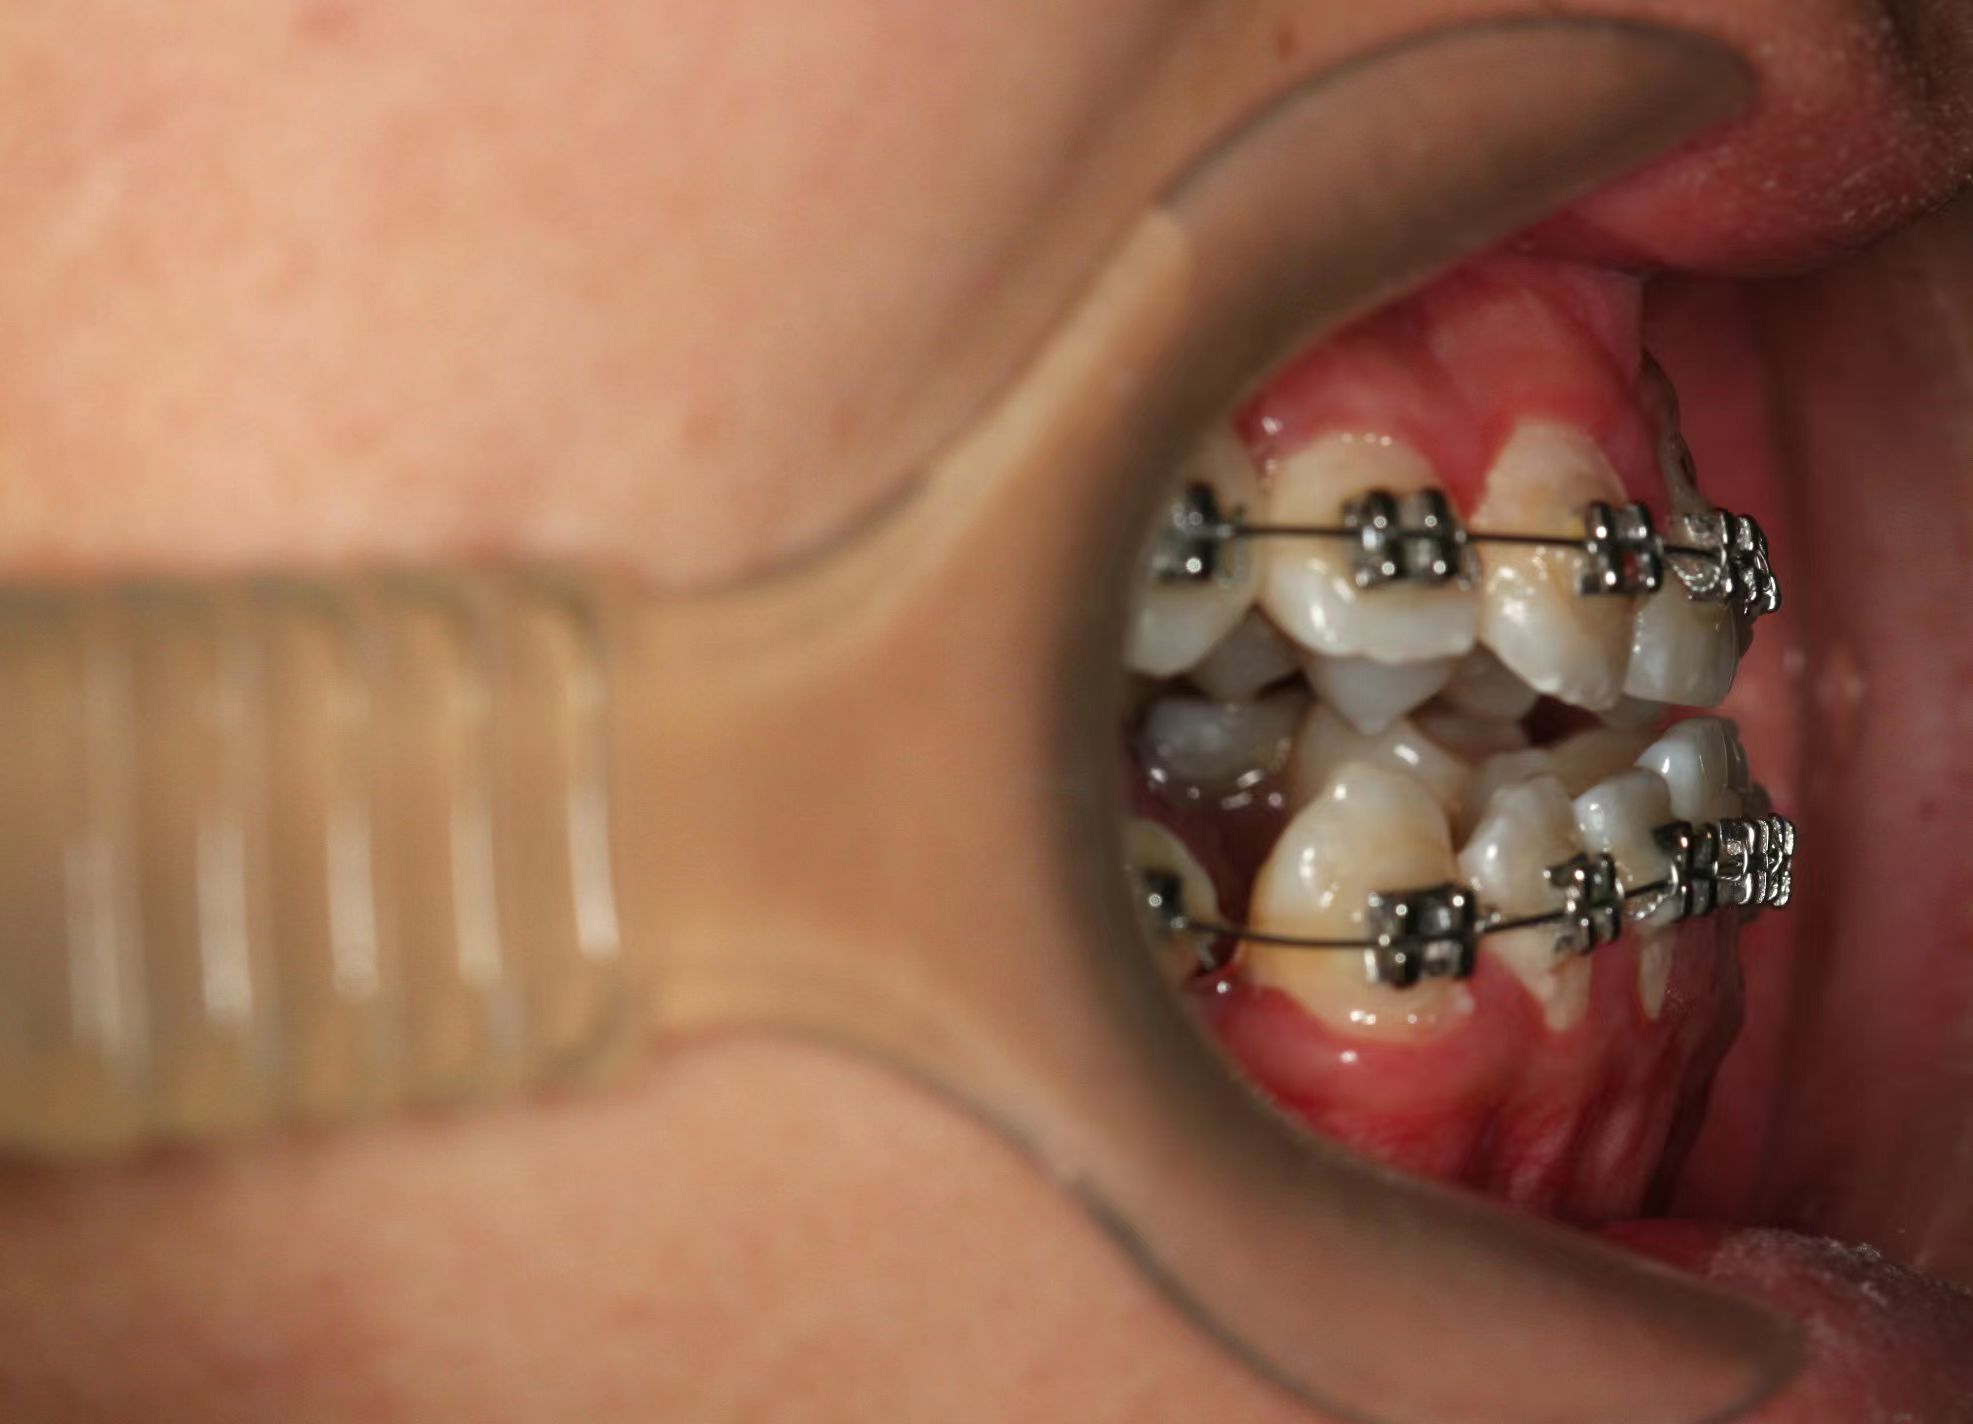

情况:不接受外科手术,在当地做了1年半的矫治,遇到困难无法进行。由外地正畸同行推荐来上海寻求非手术矫治的二手病例。武广增老师接收时的错合畸形情况,呈现严重的骨性反合偏合及侧方开合(图1-图10)。由于推荐其去口腔医院接受正颌外科手术遭到拒绝,武广增老师通过专业的检查、分析,制定一套详细的治疗计划,采用了磨牙推进器技术、武式辅弓技术等特色正畸手段获得明显效果(图2-1~图2-9)。治疗结束后也拍摄了相关照片(图3-1~图3-9)。

矫治前

图2